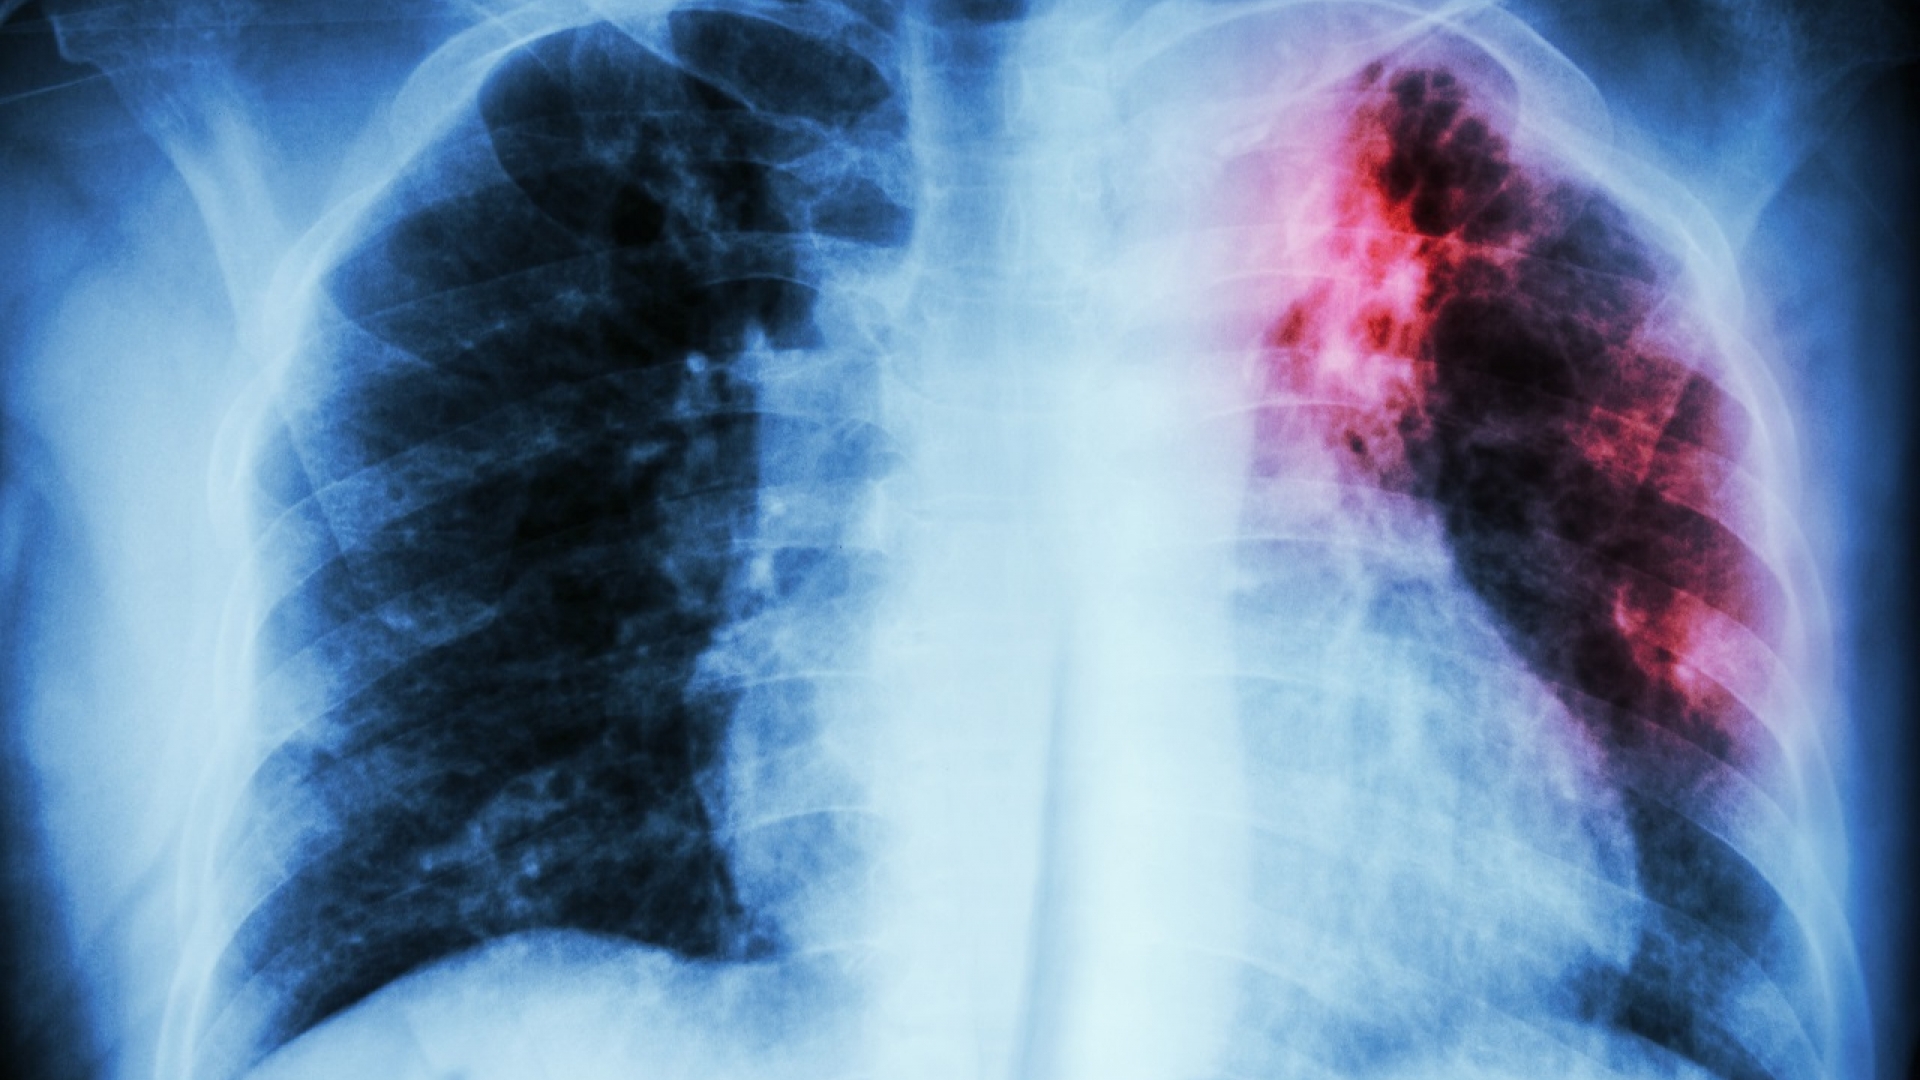

Unbehandelt kann die Tuberkulose der Lunge empfindlich schaden.

iStock.com, stockdevil

Zu den ersten Symptomen einer aktiven Lungentuberkulose gehören leichtes Fieber, Abgeschlagenheit und Husten, der über Wochen anhält. Bei schweren Verläufen kommt es später zu Husten mit Auswurf, Atemnot, Brustschmerzen und Gewichtsverlust. Unbehandelt kann die Tuberkulose der Lunge empfindlich schaden und sich über die Blutbahn auch auf andere Organe ausbreiten. Im Extremfall endet die Infektion tödlich.